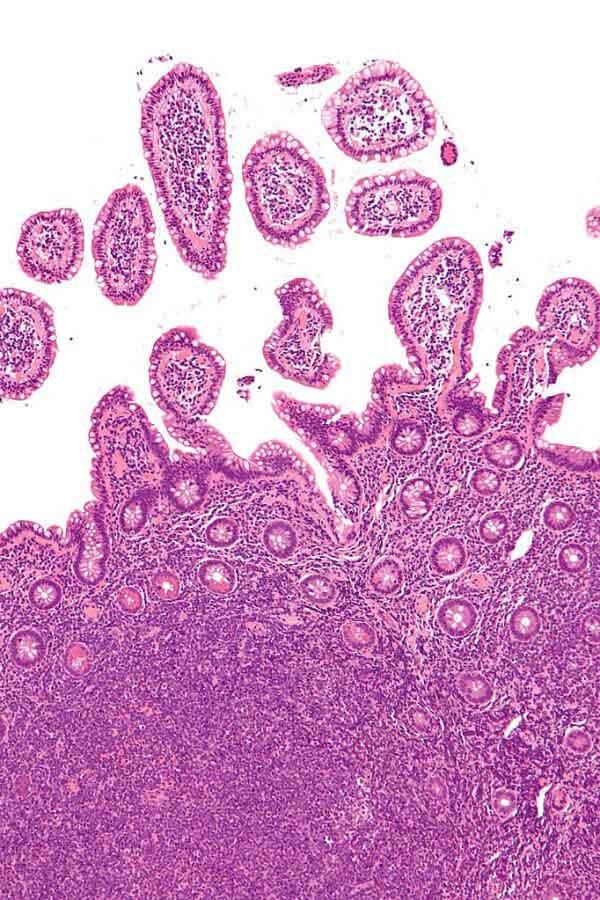

Micrografía de células de linfoma de células del manto en el intestino delgado.

Fuente: Wikimedia Commons/Nephron CC 3.0

El linfoma de células del manto es un tipo poco común de linfoma no Hodgkin que surge en las células B, que son un tipo de glóbulo blanco. A la mayoría de las personas con linfoma de células del manto se les diagnostica una enfermedad maligna y diseminada. A diferencia de otros tipos de linfomas malignos, el linfoma de células del manto es muy pocas veces curable con los tratamientos actuales.